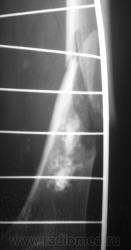

Ну, и, после "репозиции".

Что это - не скажу (под рукой нет литературы). Но. 1.Процесс опухолевый - в средней части, по заднему контуру отмечается вздутие кости. 2.Относительно длительно текущий - вздутие достаточно протяженное. 3.Пока еще относительно доброкачественный - кортикальный слой созранен. 4. Многоузловой (мультифокальный) - не менее 3-х узлов/фокусов. В зависимости от возраста/пола/анамнеза вполне может быть метастатическим. 5.Перелом все-таки патологический - линия перелома проходит через верхнюю часть патологического субстрата.

Это может оказаться и безобидным обызвествлением костного мозга после инфаркта, хондромой или хондросаркомой. - Уроки Татьяны Валентиновны. Но вздутия не вижу - его в боковой проекции симулирует третий фрагмент в месте перелома. Ну а метастаз - маловероятен... Опять же - "горим" на сочетанной патологии...

хочу поддержать доктора Анатолия Шумакова: перелом вряд ли патологический, обызвествление костного мозга бедренной кости и вероятно стенок сосудов